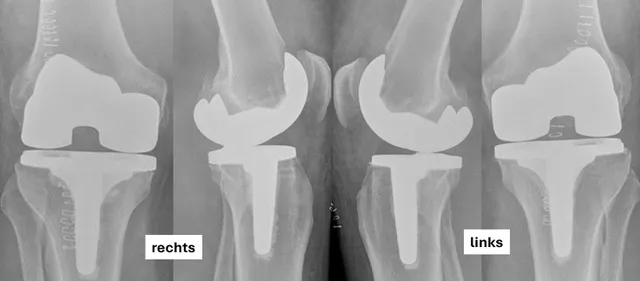

Entscheidung zur Implantation einer Knietotalendoprothese beidseits im Rahmen einer Operation mit der individuellen Origin®-Knieendoprothese. Die Planung (Abb. 1) zeigt die varischen Beinachsen von 9° bds. und die Korrekturplanung auf 2° nach der Implantation. Auf den postoperativen Röntgenaufnahmen (Abb. 2) zeigt sich eine korrekte Implantatlage.